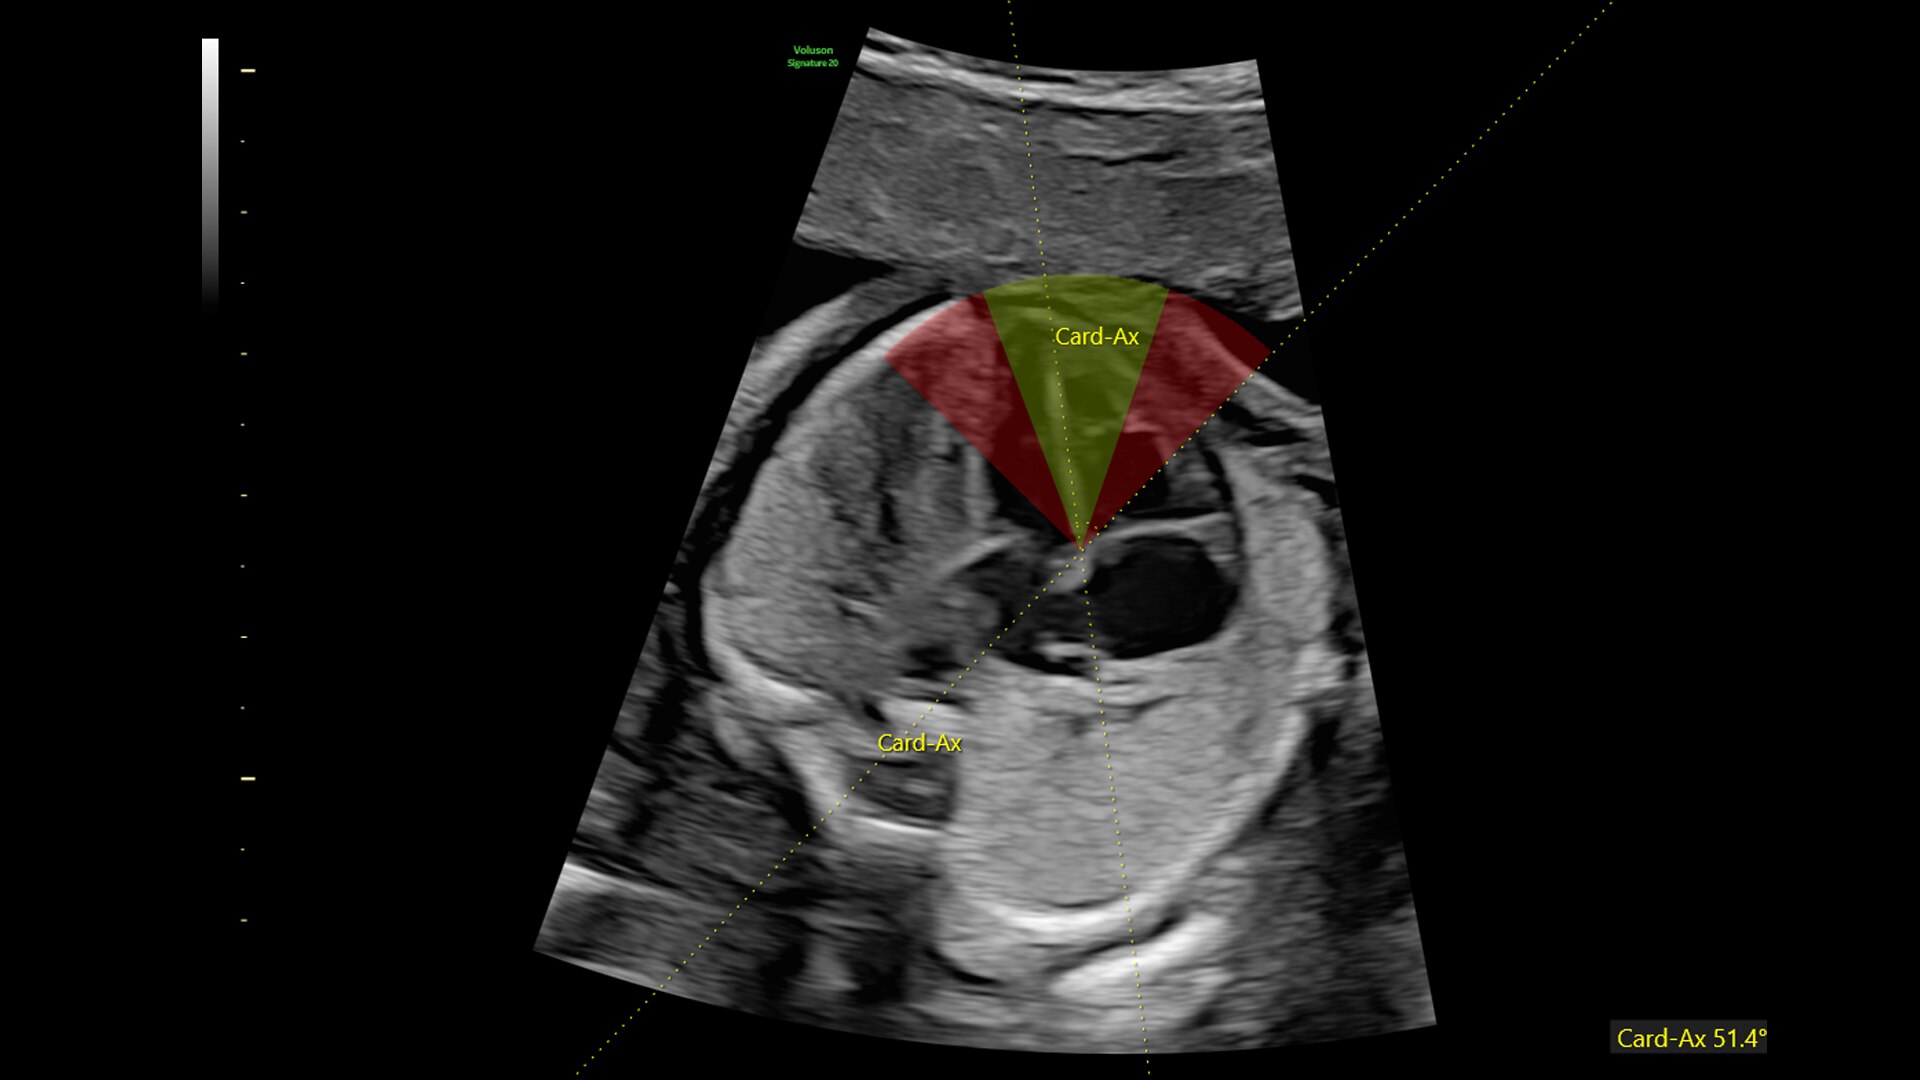

fetalHS

Reduce time to assess fetal heart by 48% with fetalHS. fetalHS provides a step-by-step guidance that uses AI to help identify fetal situs and normal fetal heart anatomy using the 4-Chamber Heart, 3-Vessel View/3-Vessels and Trachea View, and Cardiac Axis.